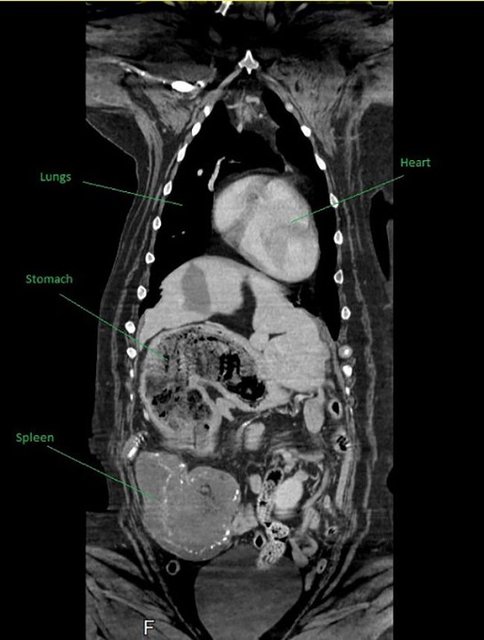

Но оказалось, что все далеко не так страшно, как подумали ветеринары, изучив снимки внутренних органов. На самом деле у Мейзи не было никакого рака: она каким-то образом проглотила четыре плюшевых игрушки, которые и вызывали проблемы в организме.

Хотя достать их было непросто, сама операция получилась куда безопаснее, чем если бы у сенбернара был рак. По словам ветеринара Ника Блэкберна, они с коллегами никак не ожидали, что найдут в животе у собаки игрушки.